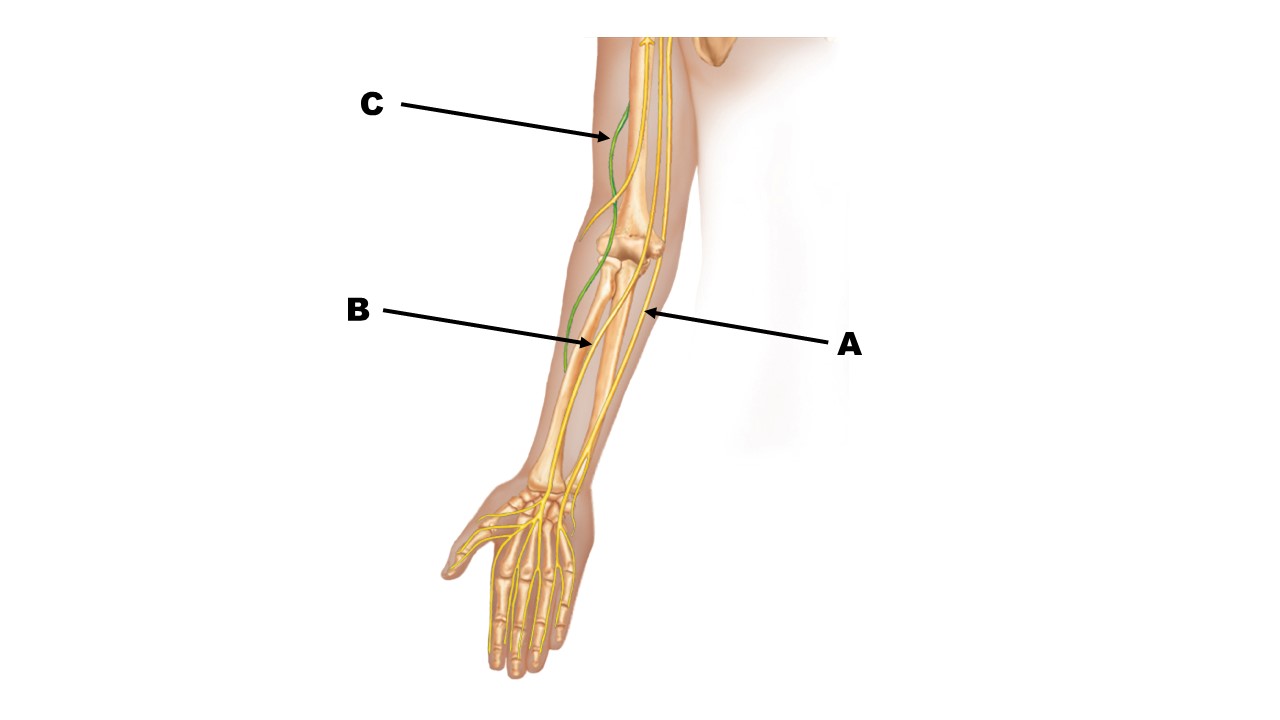

The nerve at the tip of arrow B is the _______ nerve.

The nerve at the tip of arrow A is the _______ nerve.